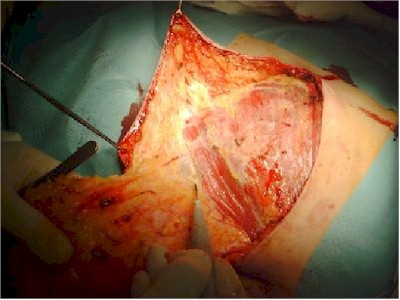

Visión del musculo pectoral mayor.

Se deja cola de la grasa de la mama, para continuar con el vaciamiento axilar en una pieza.